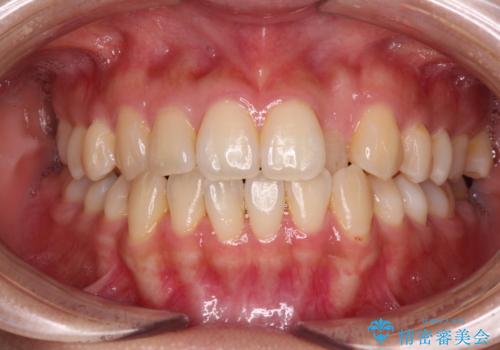

ワイヤー矯正で確実にガタつきを治したい セラミックブラケットによる治療